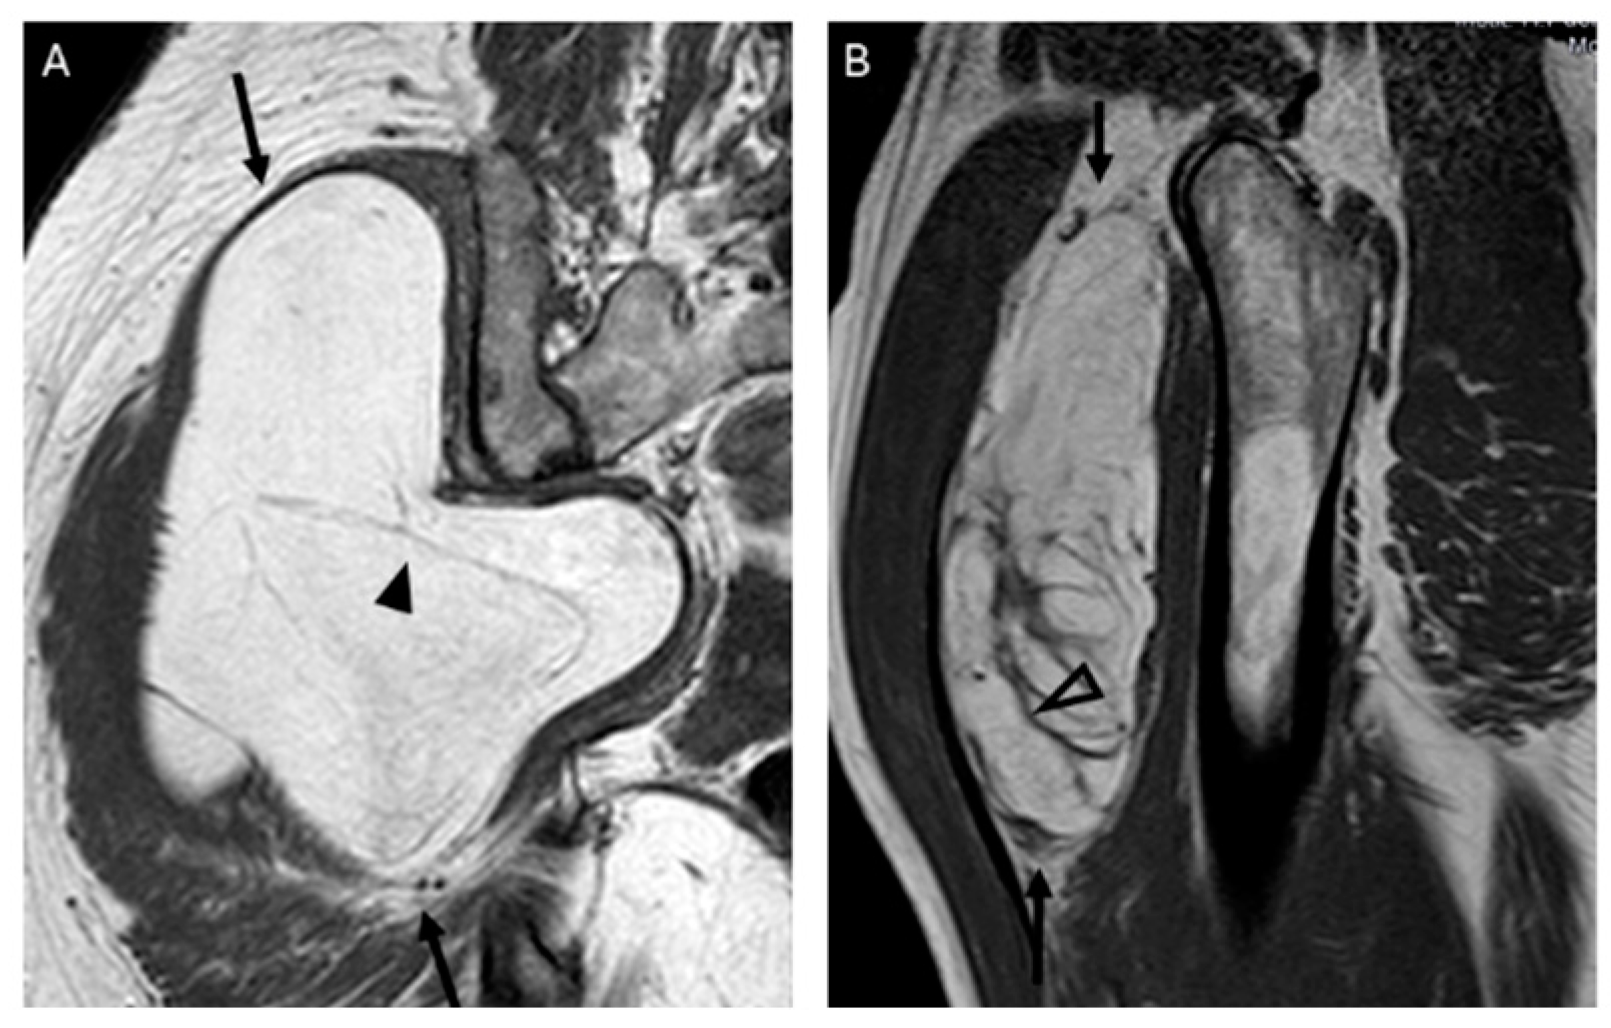

The presence and thickness of septa show significant differences between lipomas and ALTs. This one agrees with the findings of Kransdorf and Hosono, where the septa were thick and irregular in ALT/WDL and thin in lipoma [12,16]. Similarly, Brisson observed that lipomas were isointense to subcutaneous fat and may contain a few thin septa [17]. In our series, the absence of septa indicates lipoma and septa ≥ 2 mm is suggested of ALT. Septa < 2 mm can be indicative of either lipoma or ALTs (Figure 5).

Figure 5.

Septations. Coronal T1W image (A) showing a lipomatous tumor (black arrows) with thin septa < 2 mm (arrowhead) in the gluteal region. Final diagnosis: lipoma (MDM2 negative). Sagittal T1W image (B) showing a lipomatous tumor (black arrows) with thick septa ≥ 2 mm (open arrowhead). Final diagnosis: atypical lipomatous tumor (MDM2 positive).

There was typically more than one non-fat nodule in ALT, while lipomas usually had only one (Figure 6). Unlike other studies, which suggested that non-fat nodules larger than 1 cm in diameter are an important discriminator favoring ALT over lipoma [17], our findings did not support this distinction.

Figure 6.

Nodules. Sagittal T1W images show a deep lipomatous mass in the popliteal fossa, measuring 27 cm along its long axis and with two non-fat nodules (arrows) Diagnosis: ALT (MDM2 positive). Axial T2W images present a lipomatous tumor in quadriceps, with two non-fat nodules (asterisks) Diagnosis: ALT (MDM2 positive).